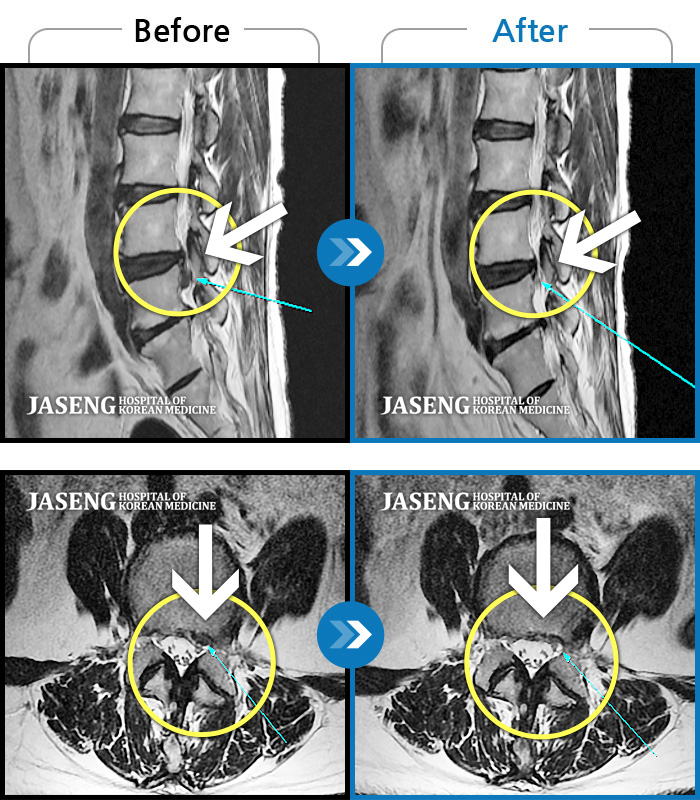

MRI 치료사례

허리디스크

분당 · 진은석 원장

교통사고로 인해 기존의 퇴행성 디스크가 파열되어 극심한 경추의 통증과 손의 힘 빠짐, 손가락의 저림 증상을 호소하였음

촬영시기

2024.04.20 ~ 2024.11.02

허리가 끊어질 것 같은 통증에 앉거나 눕기도 어려운 상태였습니다. 또한 양쪽 다리 모두 다리로 내려가는 방산통이 심했습니다.

2021.05.17 ~ 2021.11.17

허리 통증 및 좌측 다리 마비 증상

2019.03.25 ~ 2019.11.04

허리통증과 좌측 엉덩이에서 다리까지 방사통, 야간통

2018.12.27 ~ 2019.07.06

추간판 파열로 흘러내린 디스크가 신경을 자극

2017.12.06 ~ 2018.07.10

허리 통증으로 보행, 거동 불편

2016.05.20 ~ 2017.01.05